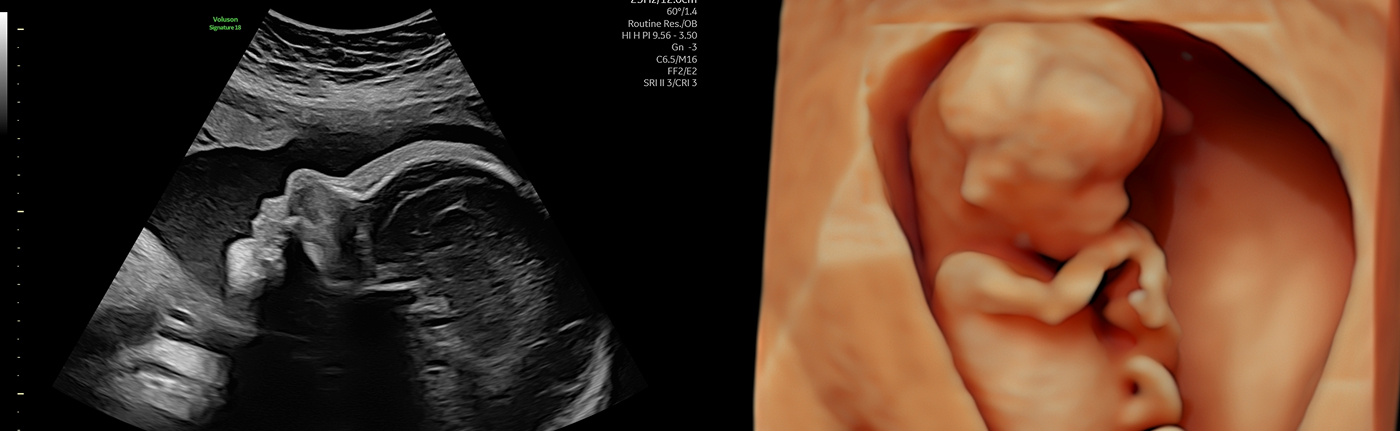

태아 정밀초음파 입체초음파

태아의 성장 발달과 해부학적 구조를 세밀하게 관찰하며, 뱃속 아기의 생생한 모습을 입체 영상으로 만나는 특별한 시간입니다.

고해상도 첨단 초음파 장비를 통해 작은 이상까지 꼼꼼하고 정확하게 확인합니다.

입체 초음파 (3D)

양수량이 풍부하고 태아의 피하지방이 발달하는 시기에, 아기의 얼굴과 표정, 움직임을 실제 사진이나 영상처럼 입체적으로 확인합니다. 출산 전 아기와의 애착을 깊게 형성할 수 있는 감동적인 검사입니다.